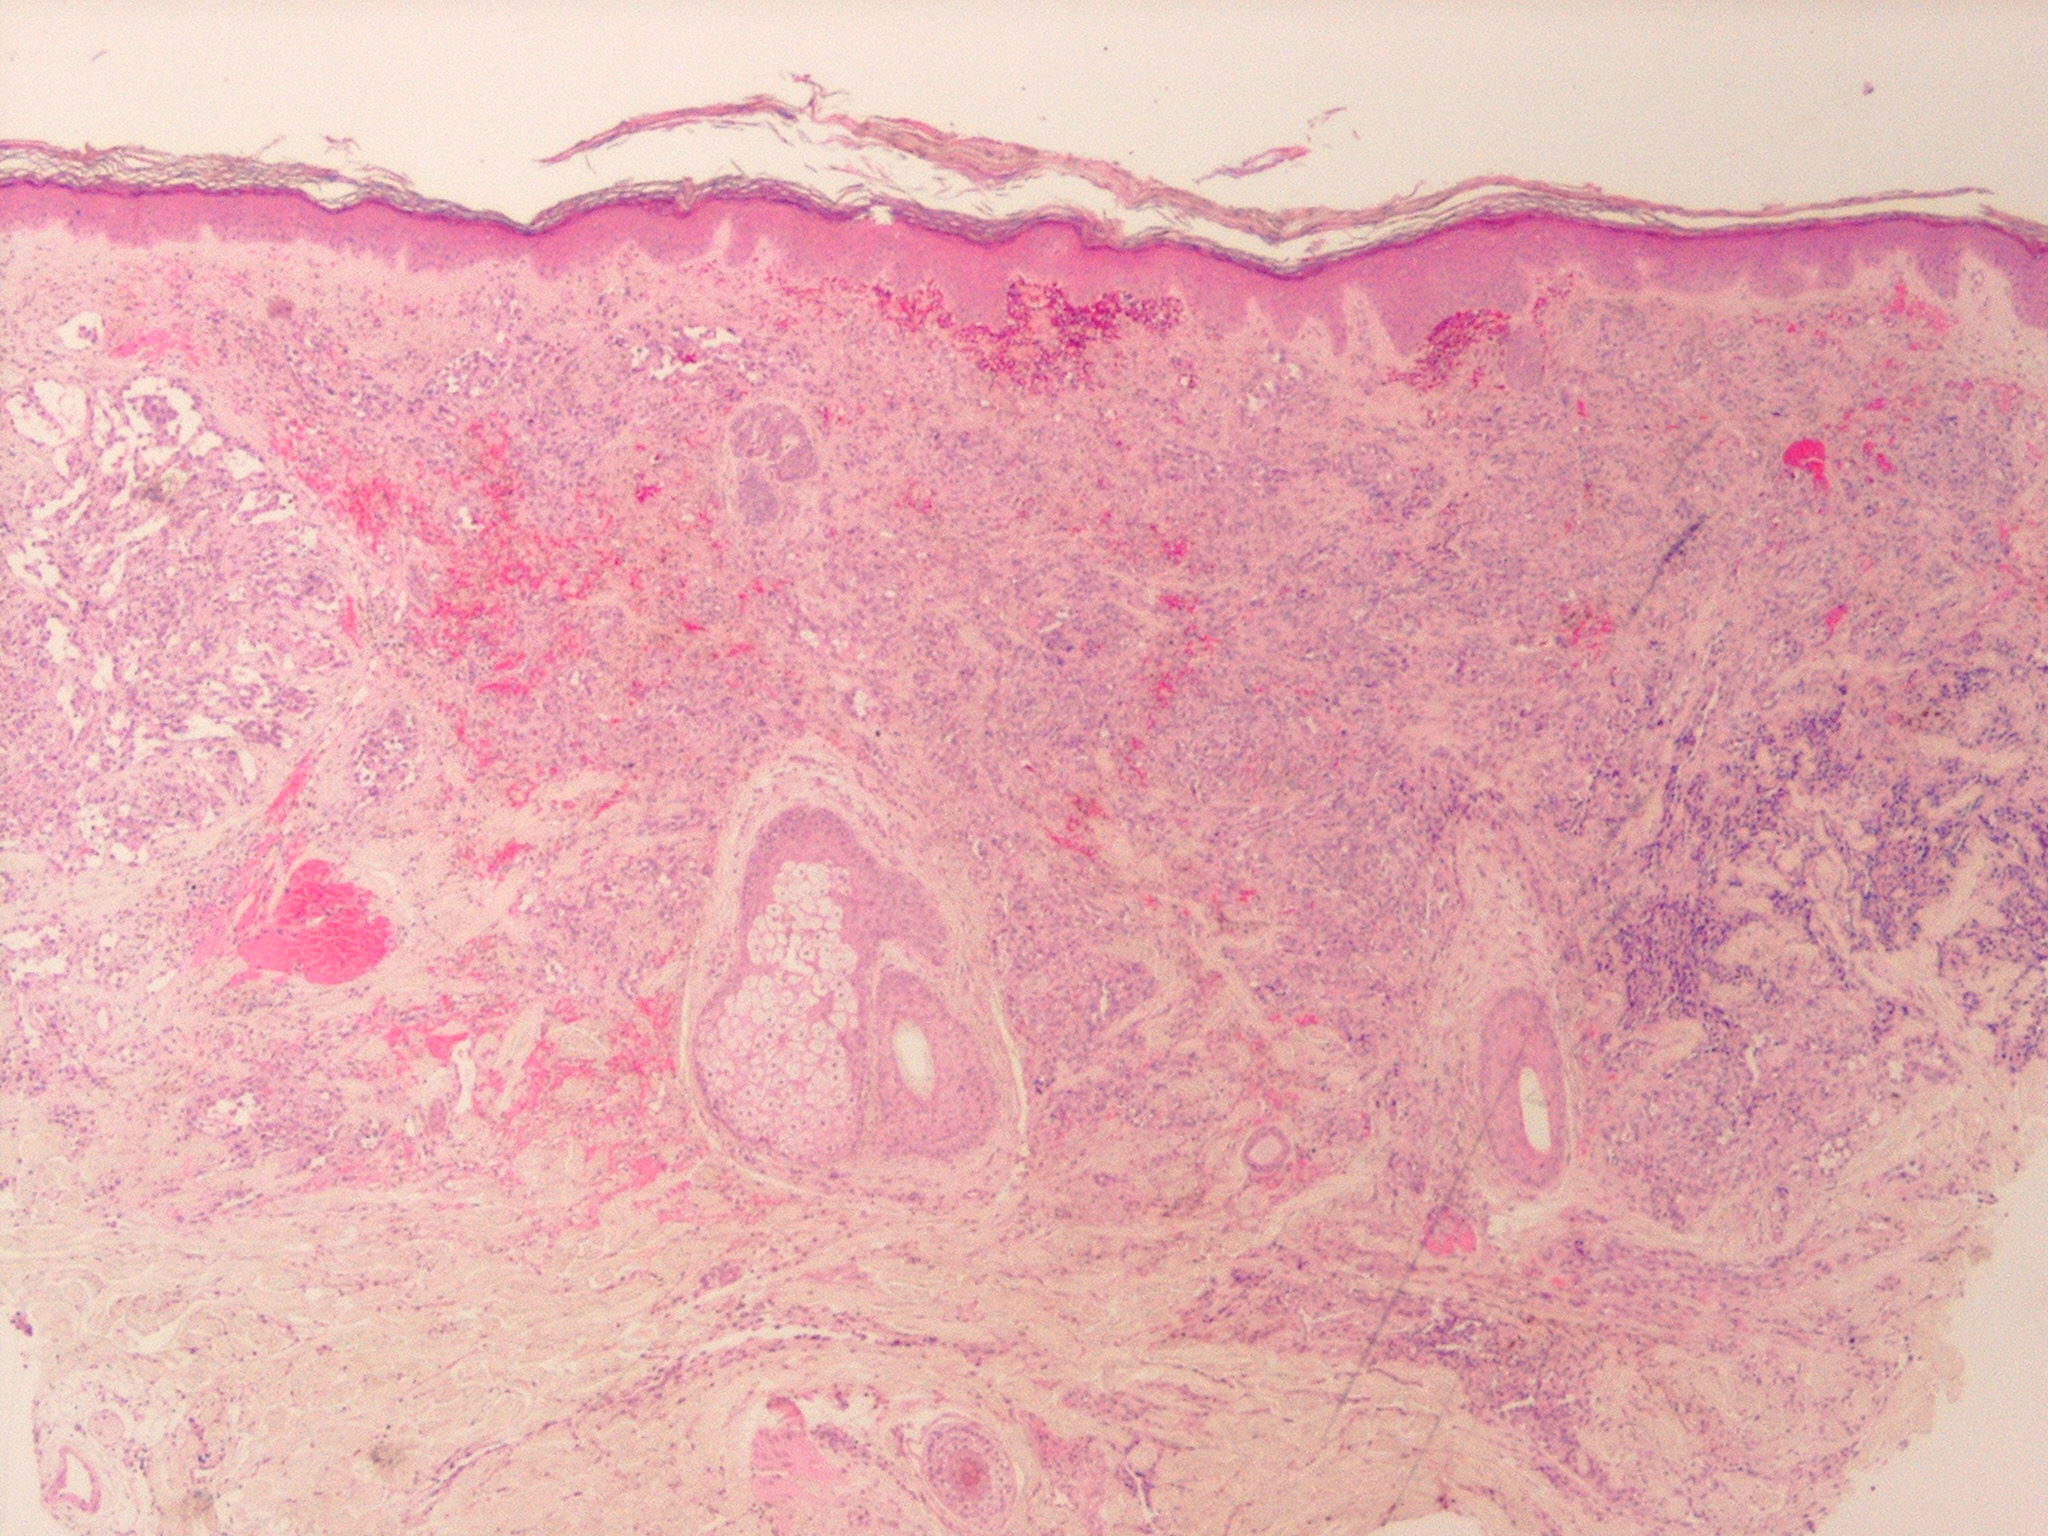

Angiosarcoma = الساركوم الوعائي